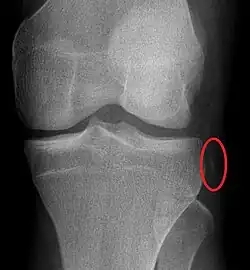

Plain X-rays, CT scan, ultrasonography, or MRI may help with the diagnosis.[2][11] Findings on X-ray that may be useful among those who have already reduced include a variable joint space, subluxation of the joint, or a Segond fracture.[5]

They may be divided into five types: anterior, posterior, lateral, medial, and rotatory.[4] This classification is based on the movement of the tibia with respect to the femur.[11] Anterior dislocations, followed by posterior, are the most common.[2] They may also be classified on the basis of which ligaments are injured.[2]